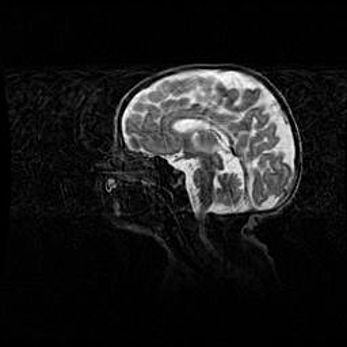

Наружная гидроцефалия с возможной атрофией височных областей.

Возраст: 28 дней

Вес: 3670 г

Пол: мужской

Окружность головы: 38 см

Срок гестации: 40 недель

Гидроцефалия головного мозга у новорожденных – это заболевание, которое характеризуется скоплением избыточного количества спинномозговой жидкости в желудочковой системе головного мозга в результате затруднения её перемещения от места выработки к месту поглощения в кровеносную систему или вследствие нарушения абсорбции. При открытой наружной форме гидроцефалии у новорожденных расширяются и переполняются субарахноидные пространства.

При нормотензивных  формах,  которые,  как  правило,  являются  следствием  перенесенных ишемических  повреждений  паренхимы  мозга,  возможно  сочетание микроцефалии  с нормотензивной гидроцефалией. В основе данных изменений лежит атрофия больших полушарий с преимущественной  локализацией  в  лобно-височных  областях.